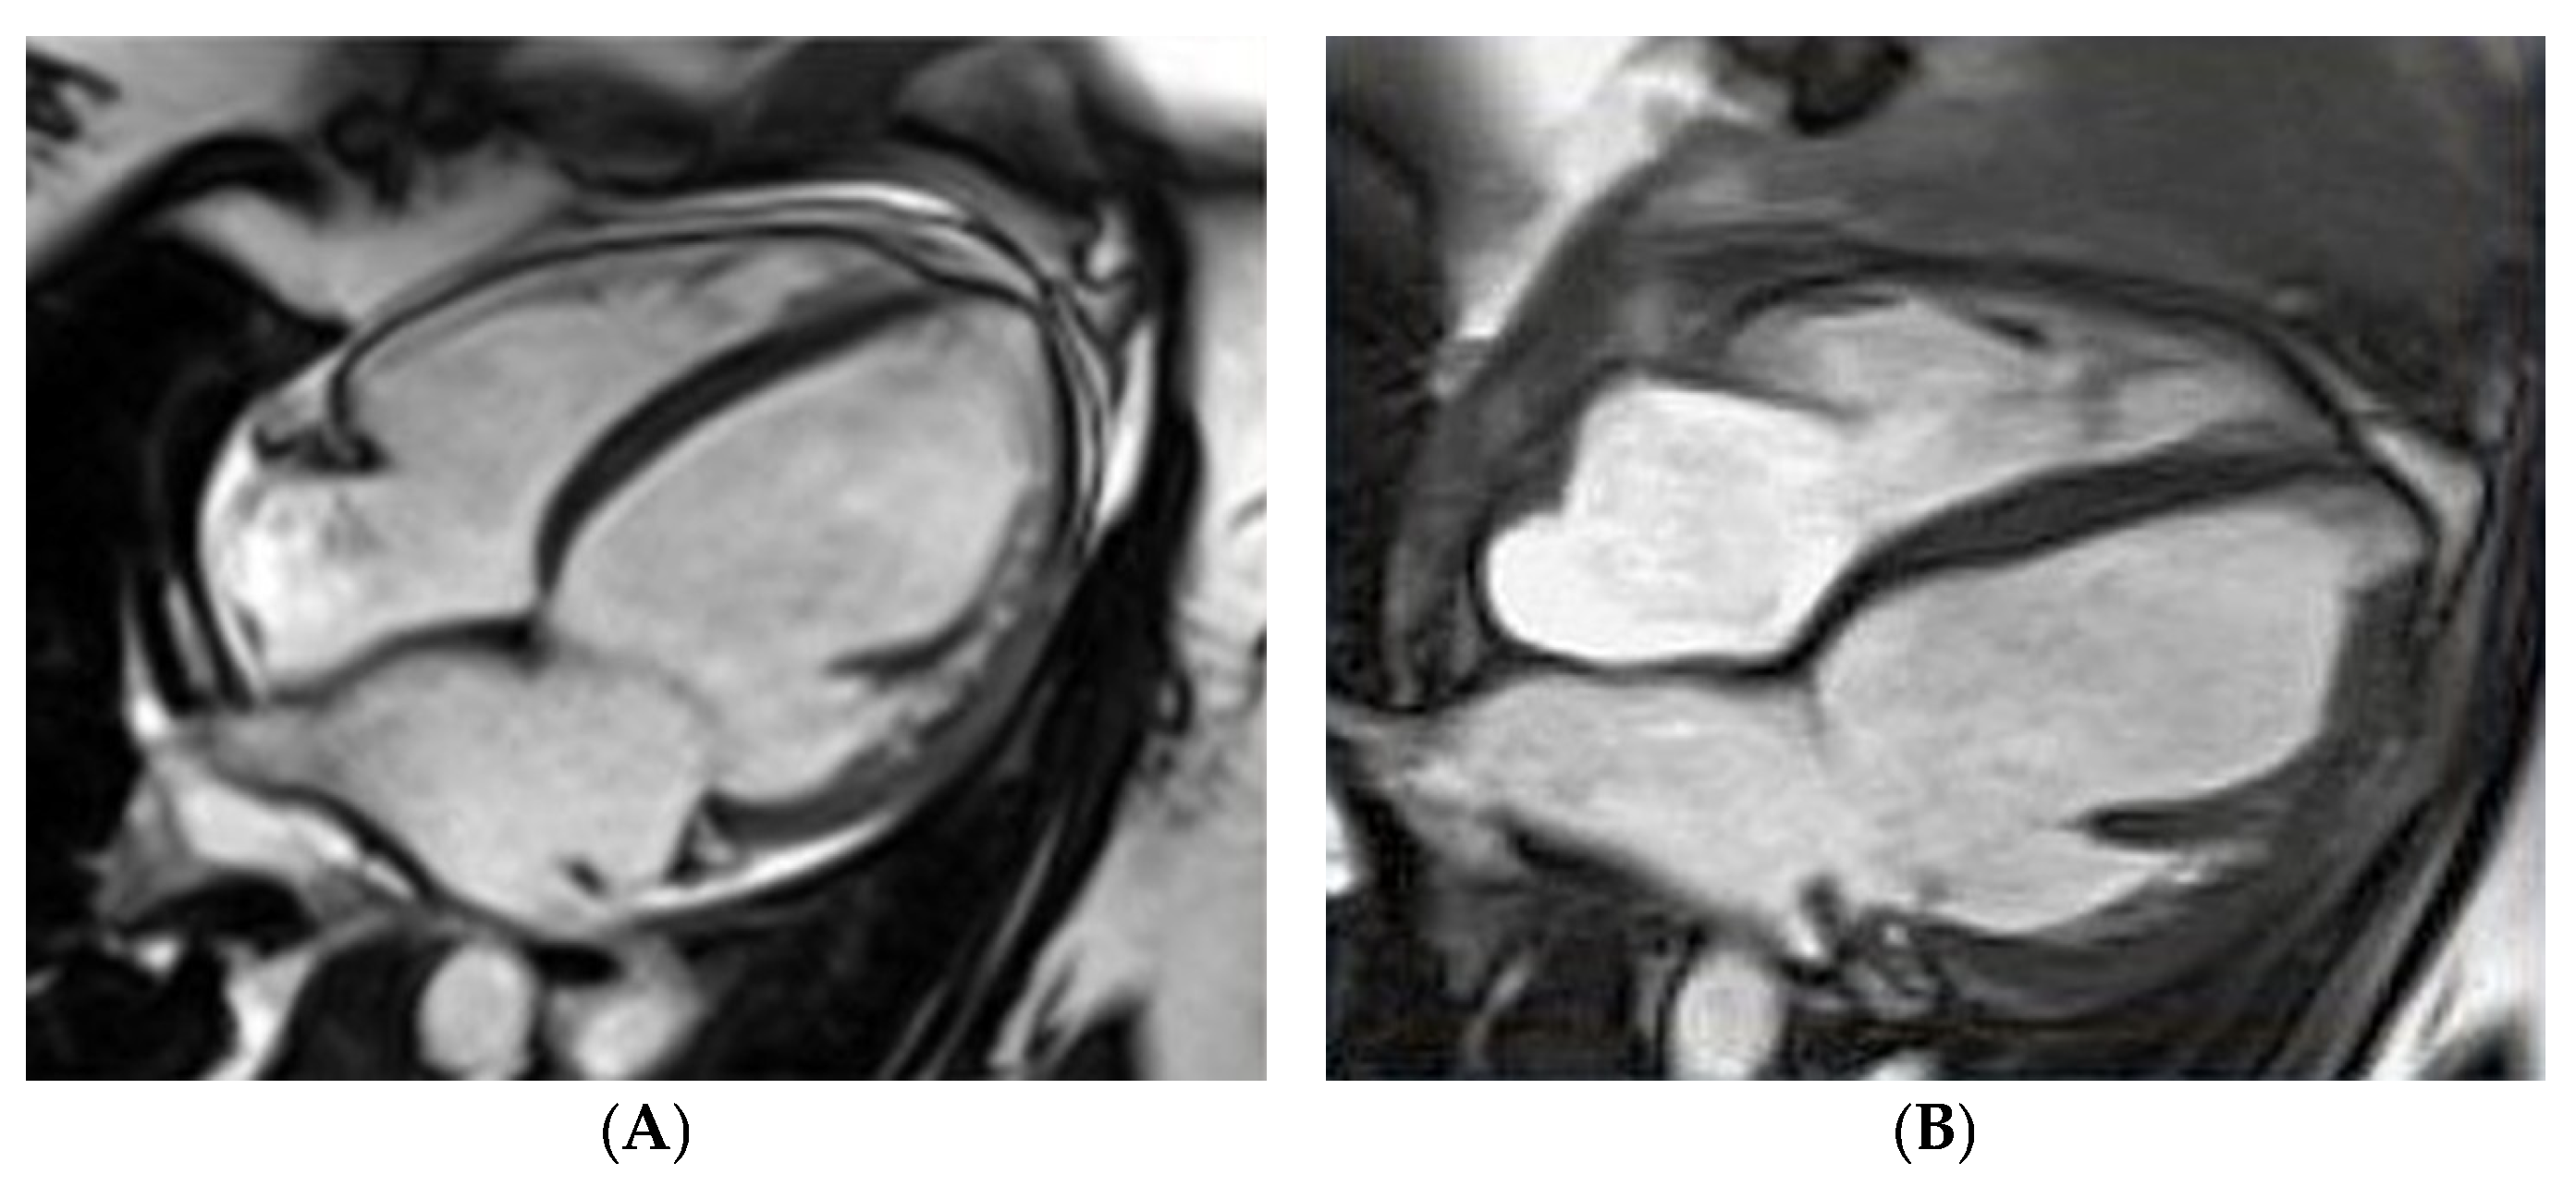

- Petryka-Mazurkiewicz, J.; Kryczka, K.; Marona, M.; Kuriata, J.; Sitkowska-Rysiak, E.; Konopka, A.; Marczak, M.; Kołsut, P.; Kuśmierczyk, M.; Demkow, M.; et al. Cardiovascular magnetic resonance imaging of biventricular assist device-induced recovery from acute heart failure in peripartum cardiomyopathy. Kardiol. Pol. 2020, 78, 1284–1285. [Google Scholar] [CrossRef]

- Petryka-Mazurkiewicz, J.; Kryczka, K.; Mazurkiewicz, Ł.; Miłosz-Wieczorek, B.; Śpiewak, M.; Marczak, M.; Henzel, J.; Grzybowski, J.; Demkow, M.; Dzielińska, Z. Cardiovascular Magnetic Resonance in Peripartum Cardiomyopathy: Comparison with Idiopathic Dilated Cardiomyopathy. Diagnostics 2021, 11, 1752. [Google Scholar] [CrossRef]